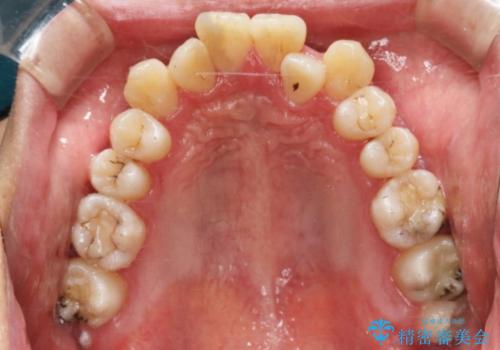

非抜歯での治療

抜歯をせずに歯のガタつきを治すためのスペースを作るために

①歯の遠心移動

②歯列弓の拡大

③IPR(歯を少し小さく削る)

この3つの方法を複合的に組み合わせて治療を行いました。